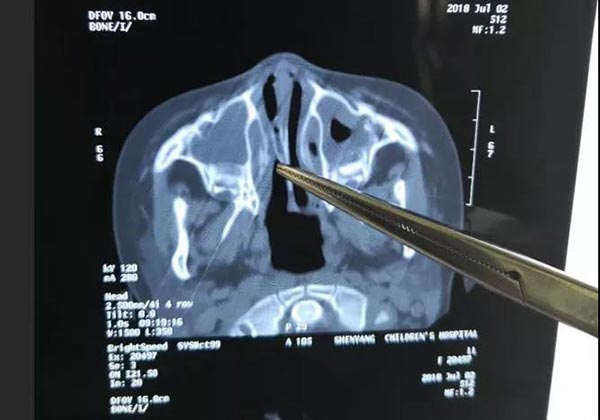

“这孩子的鼻子怎么总是臭臭的……”今年三月份的一次旅行时,妈妈就发现三岁半的小蕊蕊(化名)鼻子有些异味,还总是流鼻涕,有时候会咳嗽,一直不爱吃东西。家长带小蕊蕊先后三次去外院就诊,就以为是小感冒,吃吃药,打打针,但症状一直没有消失。直到近日前往市儿童医院就诊,经耳鼻喉门诊的医生诊治,怀疑是鼻腔异物,经过鼻CT检查,就锁定了是右侧鼻腔异物。通过手术终于取出了这个困扰了小蕊蕊四个多月的“元凶”—一个“H”形的小粘贴。

耳鼻喉科主任张新利介绍,这个异物是一个约1平方厘米大的小粘贴,有一定粘性,折叠着粘贴在了鼻腔中后部,由于比较薄,没有太影响鼻腔通气度,所以孩子没有太明显的不适反应。但毕竟是异物,刺激鼻粘膜不断地分泌鼻涕来保护鼻腔,时间久了,感染不断加重,就有了臭味,还导致了咳嗽和食欲不振。如果感染持续加重,还会对孩子造成更大的危害。